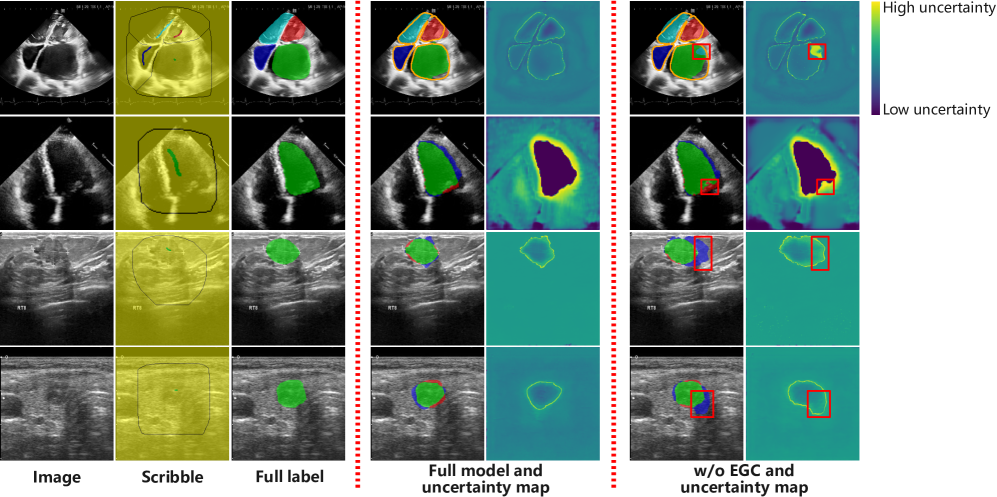

Refer to caption

Figure 9: Visualization of ablation results for the EGC strategy, comparing segmentation outputs and uncertainty maps with/without EGC across four datasets. w/o denotes without.